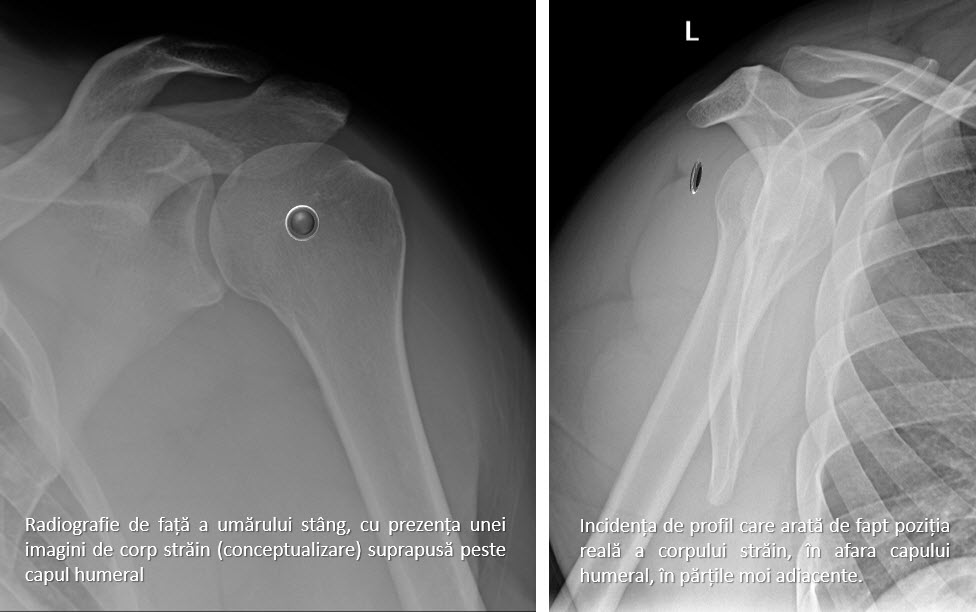

Obținerea de imagini ne-suprapuse ale corpului uman, imaginile obținute sunt “felii” (slice-uri) transversale prin corp, de diferite grosimi, obținute prin iradierea și captarea imaginilor din diferite unghiuri (practic, tubul Röntgen se rotește în jurul corpului 360 de grade și îl “fotografiază” din toate unghiurile). În linii mari, am putea spune că o computer tomografie este la baza o radiografie din toate unghiurile. De fapt, calcule complexe determină atenuarea razei X (cât de mult sau cât de puțin este absorbită radiația printr-o regiune) pentru fiecare regiune din corp și apoi computerul, pe baza complexului aparat matematic din spate, atribuie o imagine în nuanțe de gri fiecărei felii de imagine. Prin urmare, spre deosebire de radiografie care este o imagine directă (radiația care trece prin corpul uman impresionează filmul), computer tomografia este o imagine reconstruită/calculată de computer. Din acest motiv, progresele matematice și fizice aduc îmbunătățiri permanente acestei tehnologii.